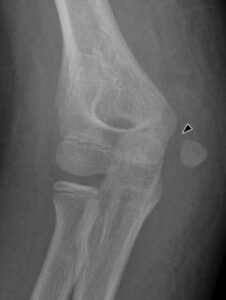

[toggle title=”Medial Epikondiler Kırıklar” state=”close”]

Çoğunlukla 10-14 yaş arası çocuklarda görülür.

Yaralanma direkt travma sonucu olabileceği gibi fleksör kas grubunun oluşturduğu avülsiyon sonucu ya da dirsek çıkığına sekonder de olabilir.

Medial epikondil kırıklarının yarısına yakınında eşlik eden dirsek çıkığı da görülür. Bu hastalarda dirsek redükte edildiğinde medial epikondil kırığı da redükte olur.

Kırık parçanın eklem içinde kalması nedeniyle redüksiyon yapılamayan durumlarda ya da kırığa eşlik eden ulnar sinir yaralanması varlığında cerrahi tedavi gerekir.